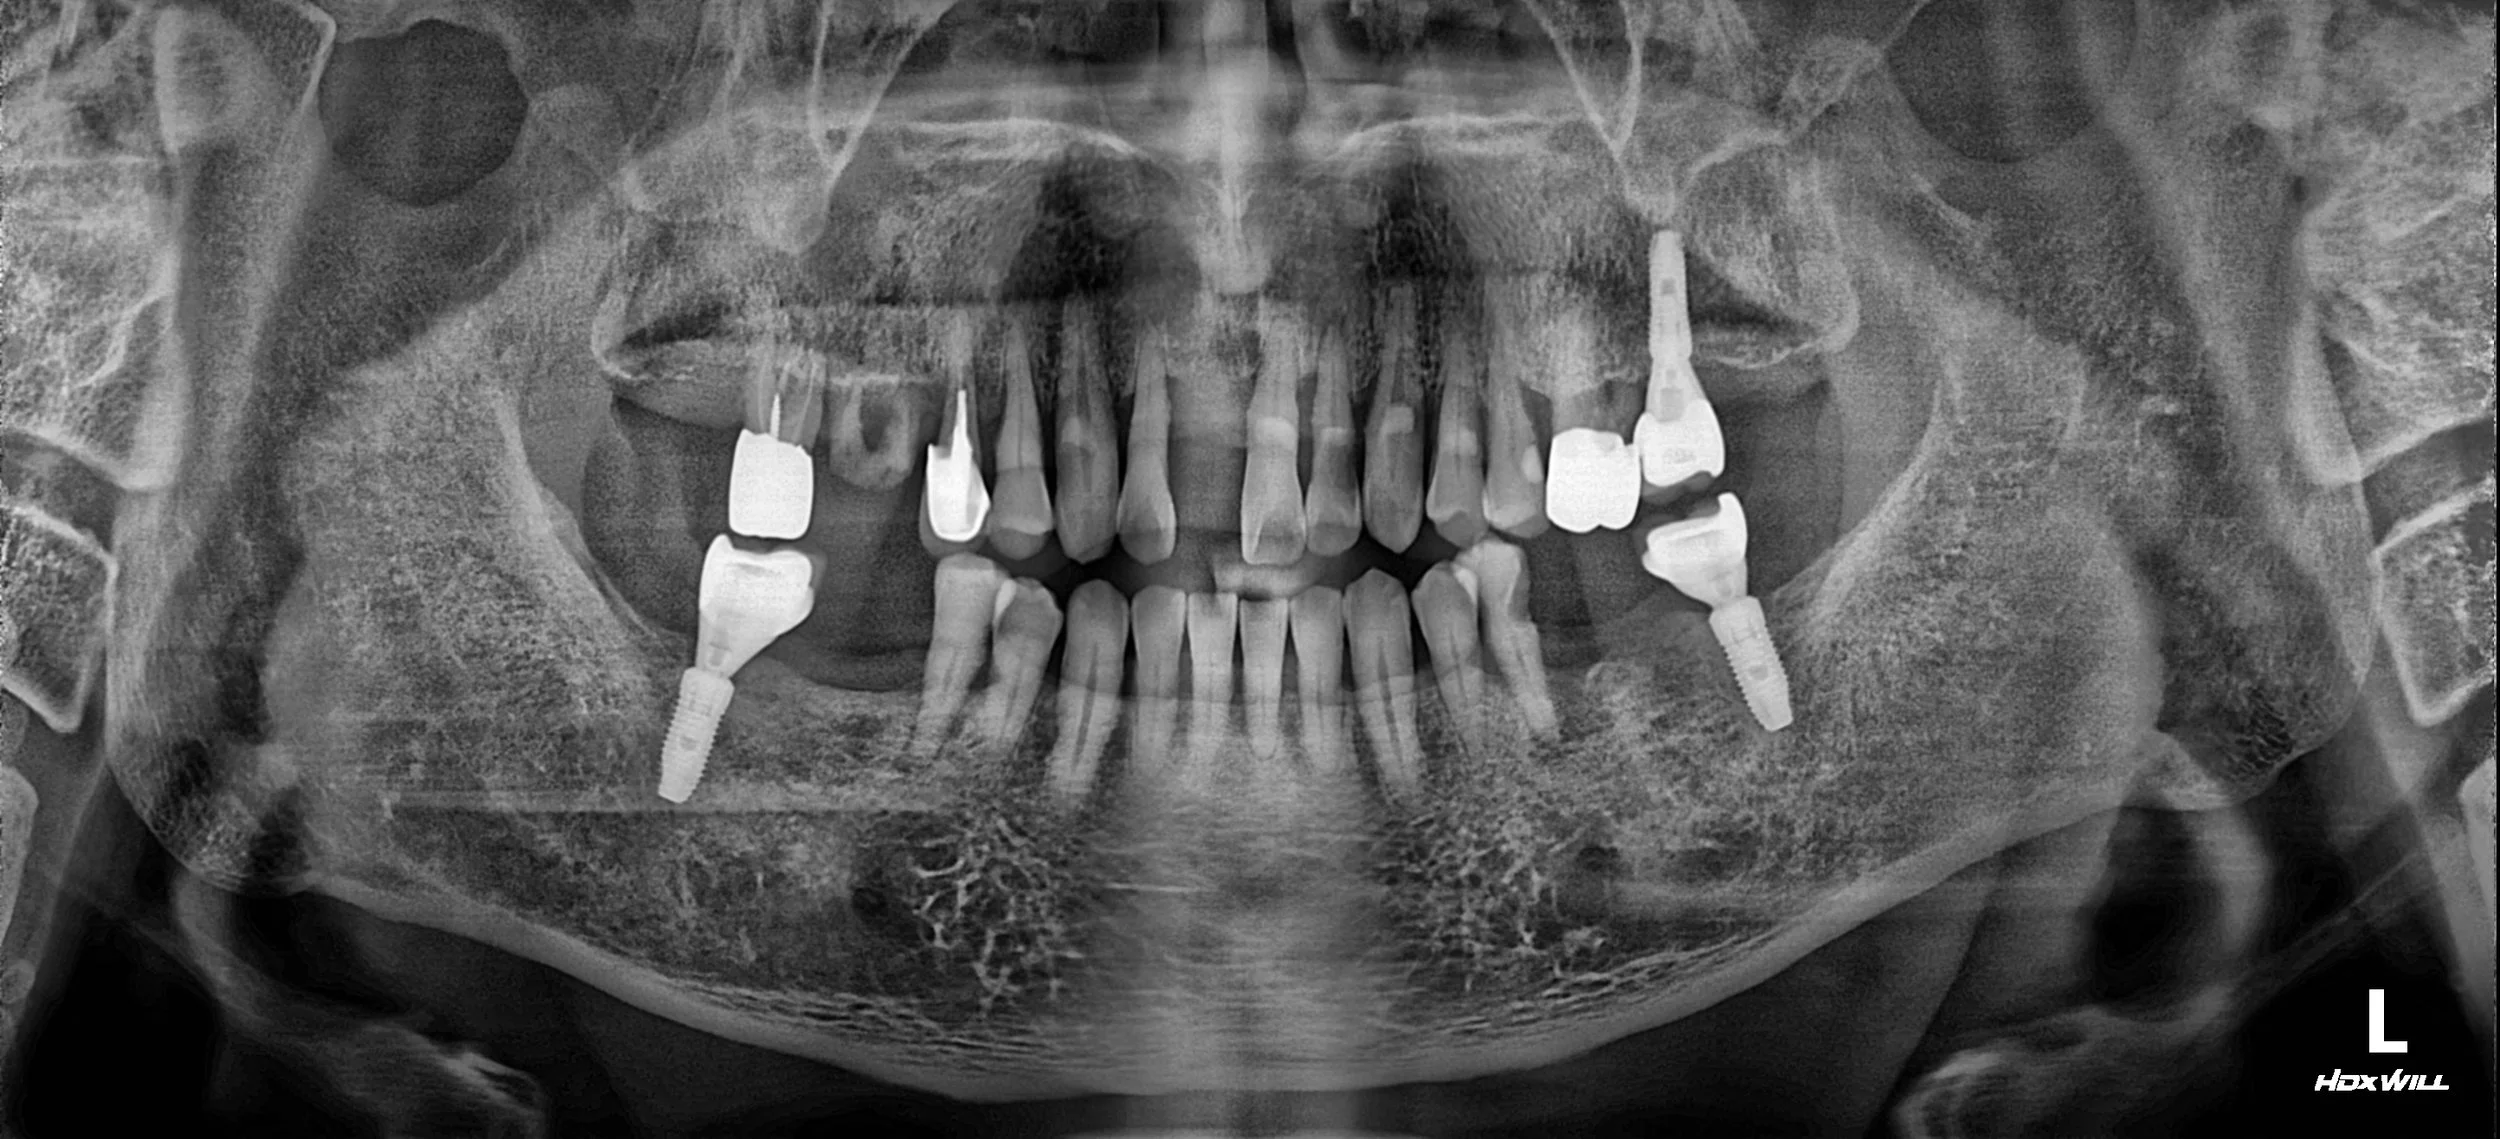

25. Comprehensive Full-Arch Rehabilitation: Re-establishing Occlusal Harmony in Advanced Periodontitis

Case Summary

A male patient in his 50s presented with advanced generalized periodontitis and multiple failing restorations. The clinical situation was complicated by:

• Severe Periodontal Disease: Extensive horizontal and vertical bone loss affecting almost all remaining natural teeth.

• Failing Existing Implants: Previously placed implants required prosthetic replacement due to mechanical failure and poor occlusal alignment.

• Disorganized Occlusal Plane: The lack of posterior support and irregular tooth wear had led to a complete breakdown of the functional occlusal relationship.

OPG - BEFORE